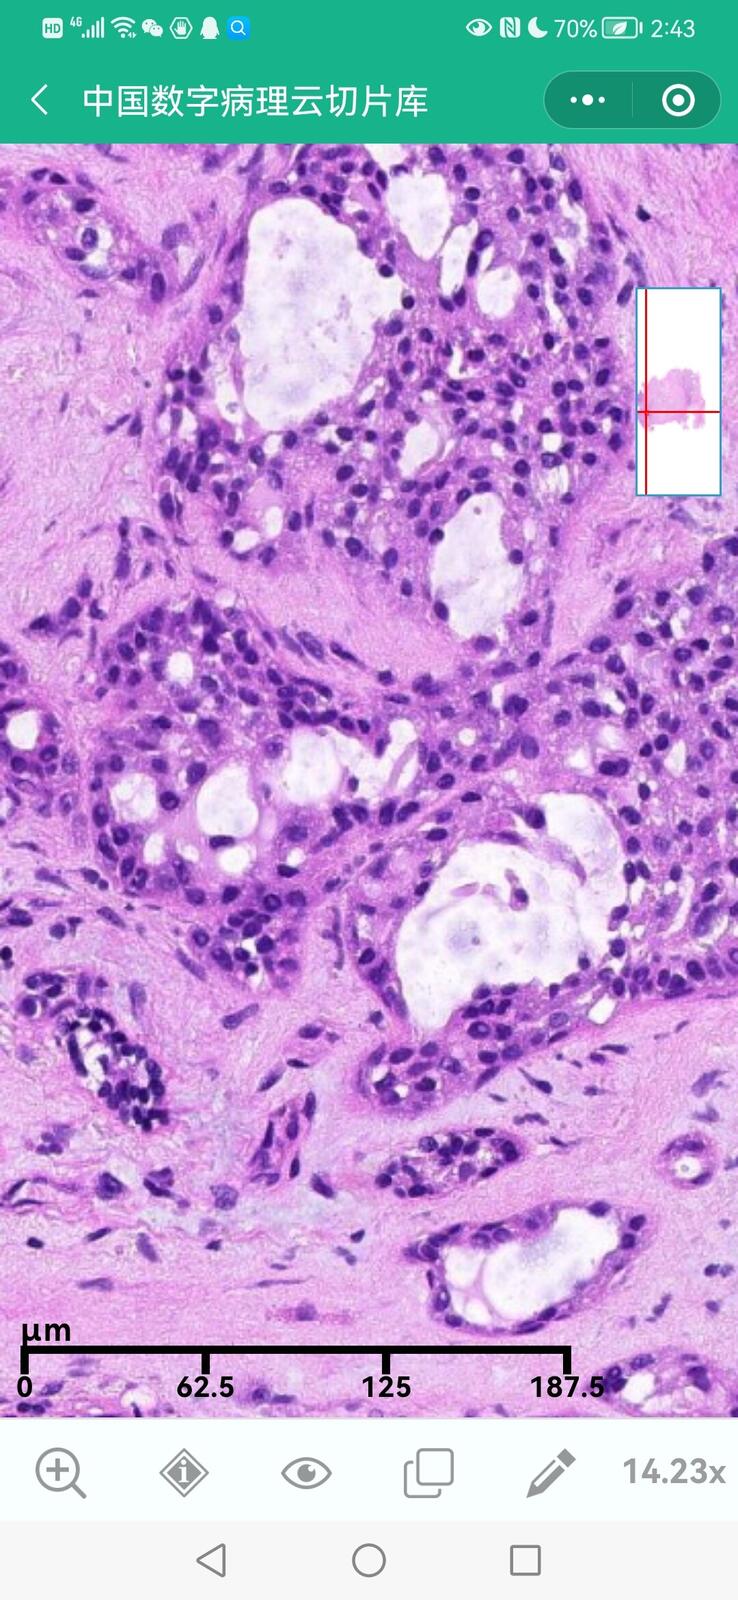

乳腺黏液性囊腺瘤伴导管内癌

乳腺多形性脂肪肉瘤

乳腺叶状囊肉瘤

乳腺分泌性癌(29岁)